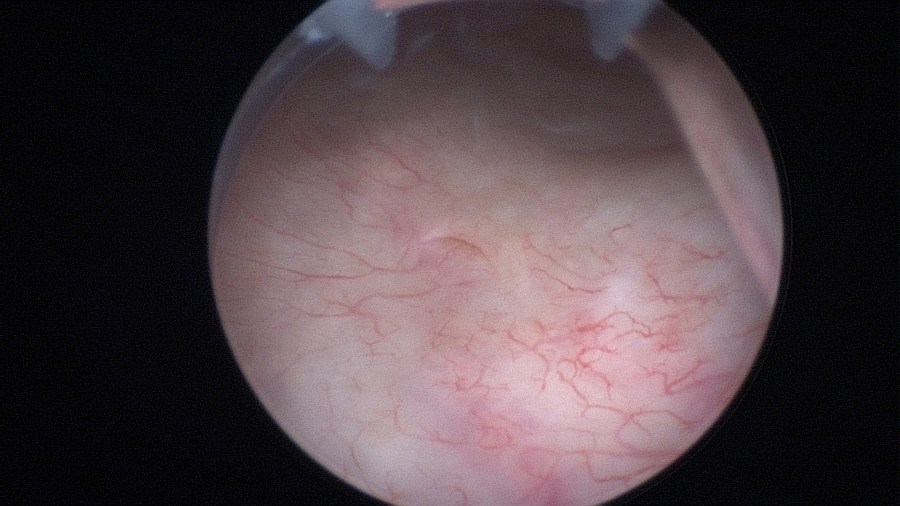

The bladder neck.

The mid-urethra.